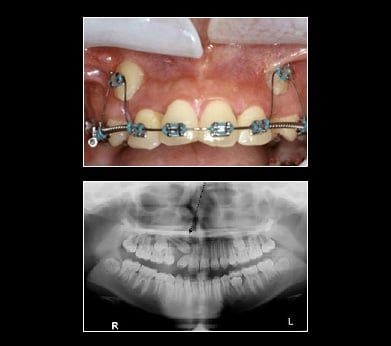

Ectopia

Ectopic canines are generally found in the Buccal Vestibule. Impacted canines may be retrieved with braces, using a surgical approach via a gold chain or straight wire. Tissue covering the tooth is uncovered. A chain or wire is attached to the tooth crown. Tissue is placed back over the tooth leaving the chain or wire coming out of the gum. For the purpose of this illustration a gold chain is used to retrieve the canines. The chain is attached to the tooth crown and the link is attached to a flexible archwire so that the wire is active (bent). Once a month, the wire is reactivated by using the next link up on the chain until the impacted canine erupts enough to attach a regular bracket on the canine. With the regular bracket in place, a more flexible wire is added directly to the bracketed canine. This process will bring the canine into position within the arch by forcing the canine to conform to the straight archwire form. This is a long process taking anywhere from 8-12 months.